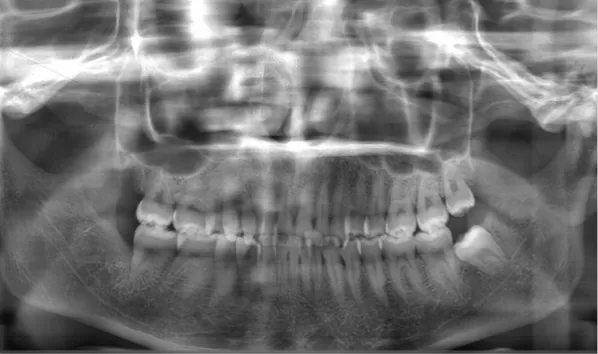

Female, 25 years old. Chief complaint: protruding and misaligned teeth, requiring orthodontic treatment.

X-rays before treatment

[Panoramic Radiography/Lateral Cephalogram]